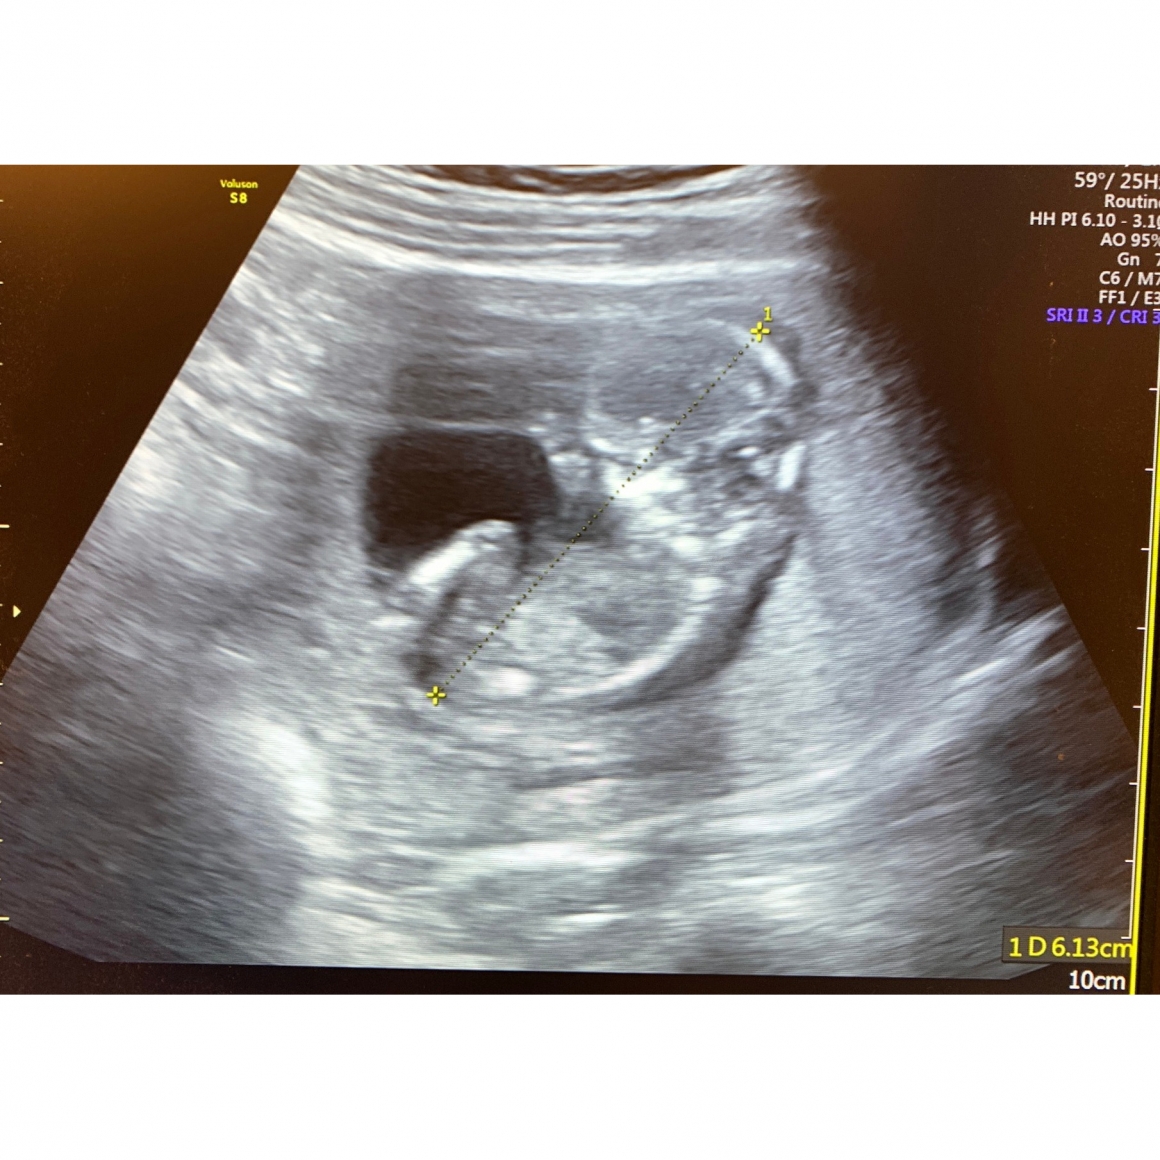

驗孕的那天,懷孕指數是1706,表示胚胎安穩地住下來了

初步產檢也都正常,很恭喜小吟從想孕門診順利畢業了